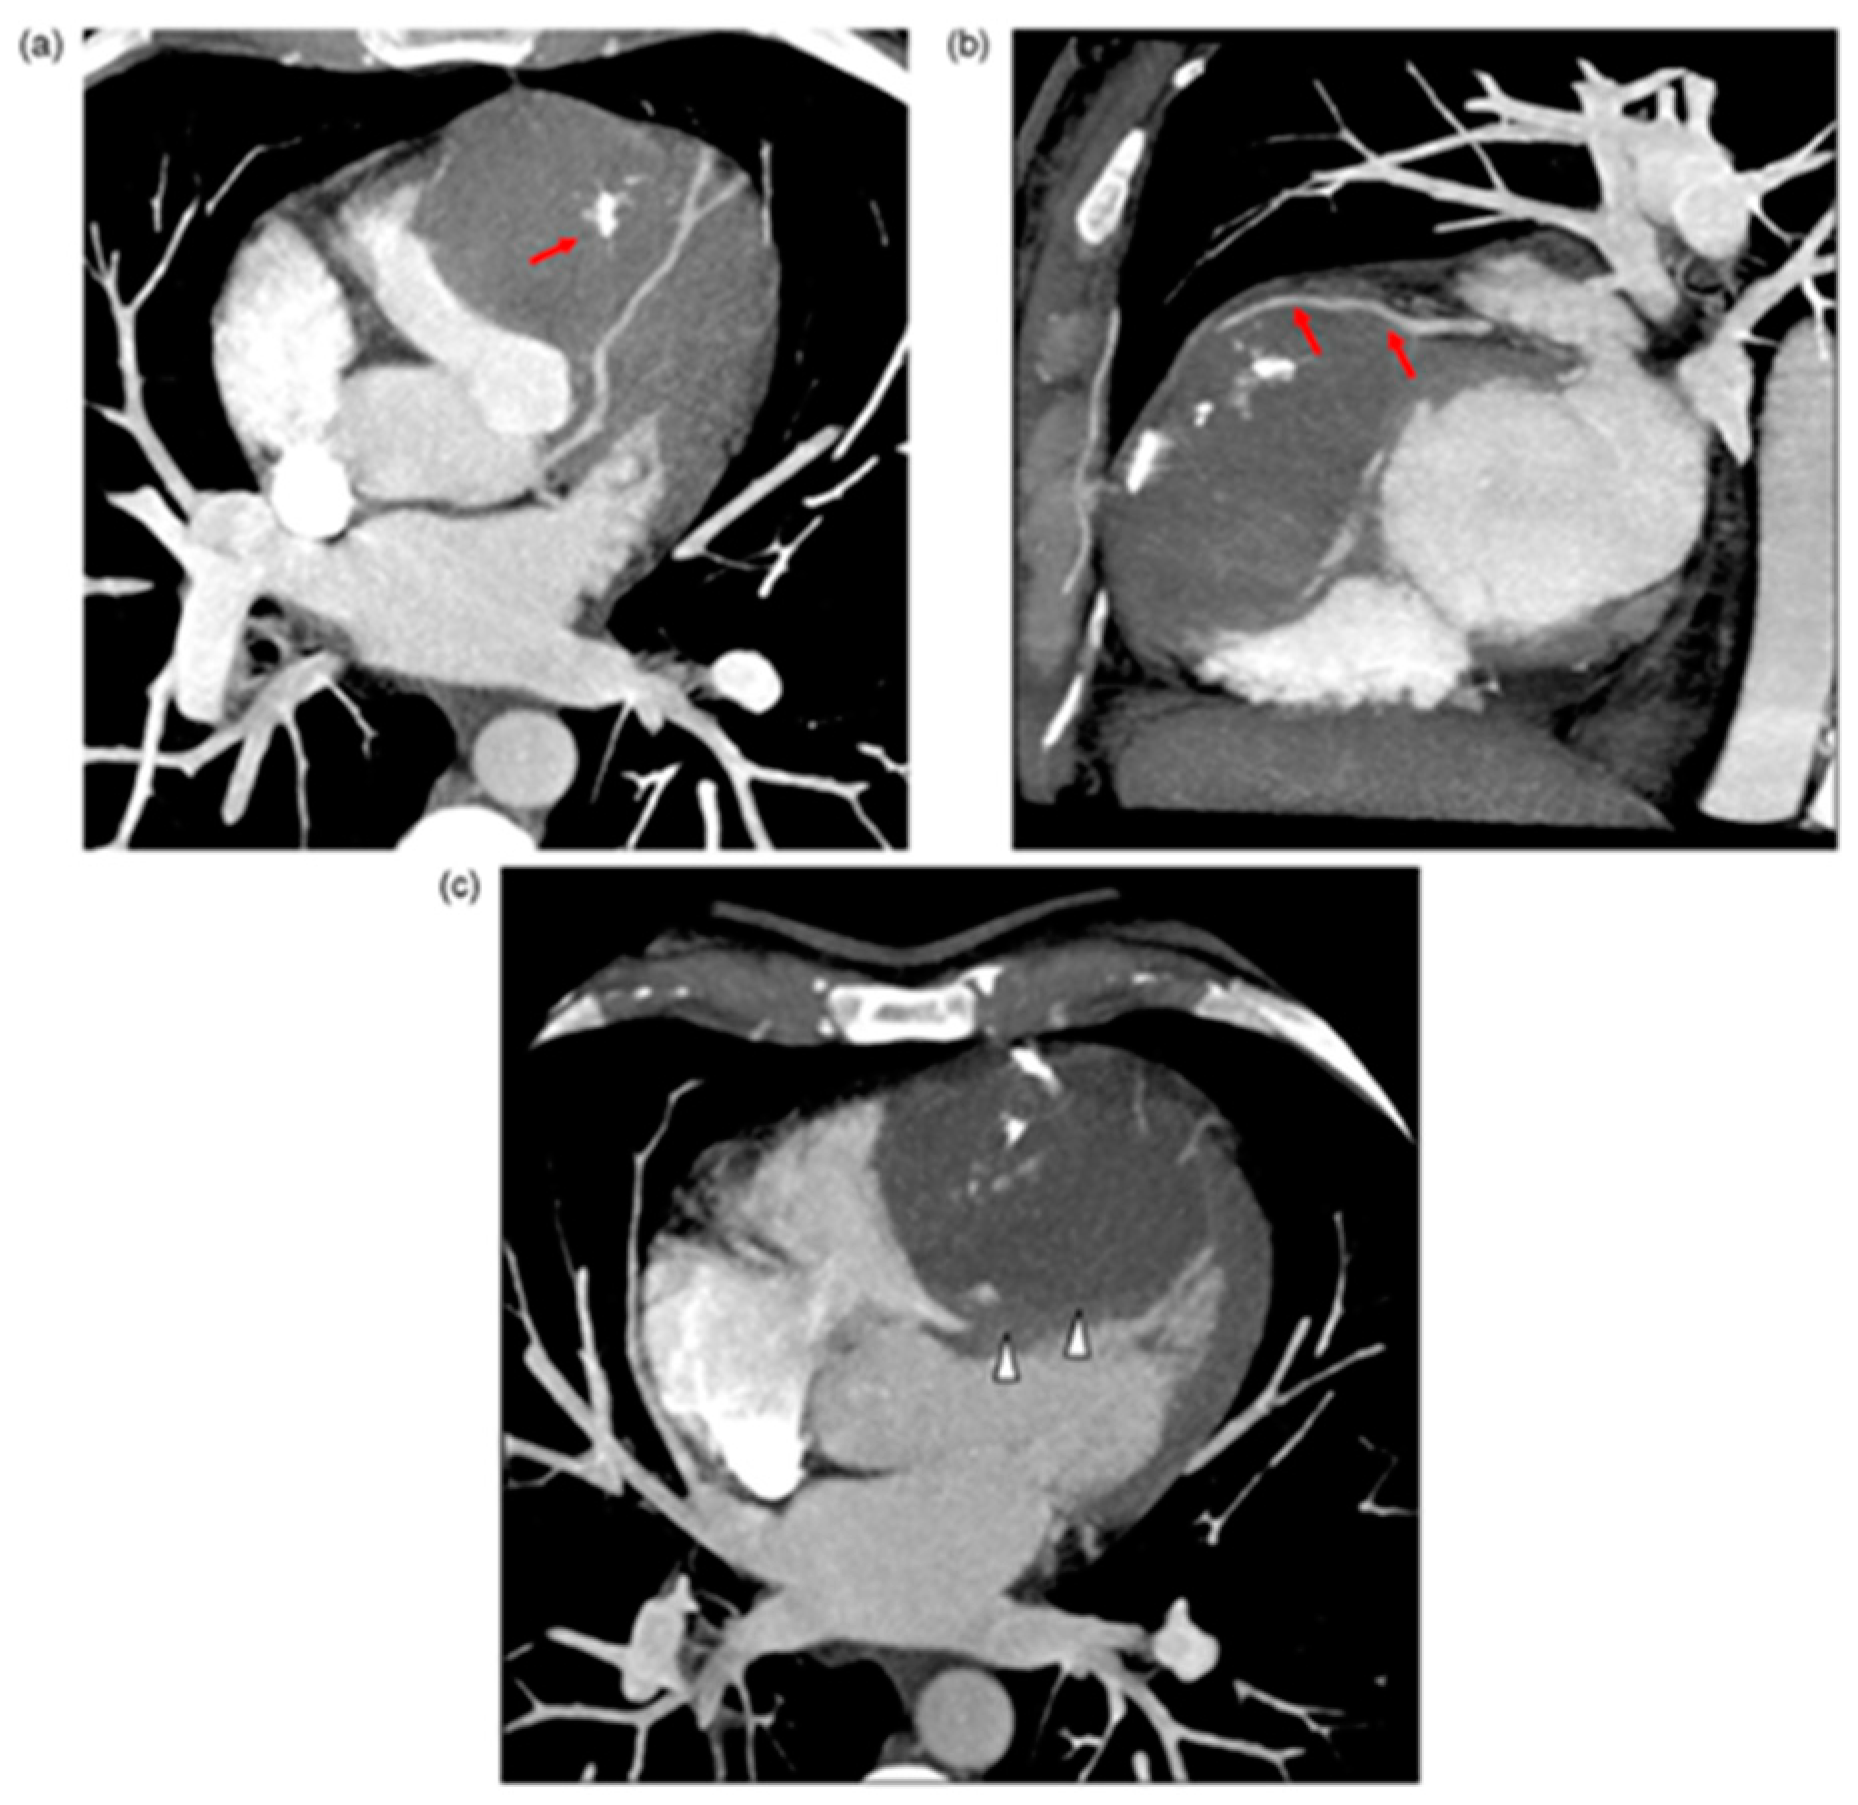

IVS abscess development usually occurs as an extension of infective endocarditis from cardiac valves and is associated with high mortality [70]. Cardiac tumours are some of the rarest primary tumours, while cardiac metastases are more common yet still relatively rare [71]. Seventy-five percent of primary cardiac tumours are benign and seldom involve the IVS. Fibromas and hemangiomas occasionally originate in the IVS and may mimic HCM (Figure 4) [72], whereas hamartomas of mature cardiac myocytes (HMCM) are hyperproliferative growth of mature cardiac cells, which are slow growing and solitary, usually present in young men in their mid-twenties in the ventricles and IVS; they may be asymptomatic.

Figure 4.

(a) Multi-detector computed tomography (MDCT) axial transverse view. Right ventricular (RV) mass occupying the ventricle and bulging out. The mass is pushing out the RV free wall. Note calcifications in the mass (red arrows). (b) MDCT right oblique short axis view. Left anterior descending artery in contact with fibrous mass tissue (arrows). (c) MDCT with multiplanar reconstruction and Maximum Intensity Pixel on four chamber view. Absence of pericardial effusion. The mass is arising from the IVS (white arrowheads); large sessile adherence on IVS. Stéphant E, et al. Eur. J. Radiol. Extra 2008; 67: e103–e106 [72].